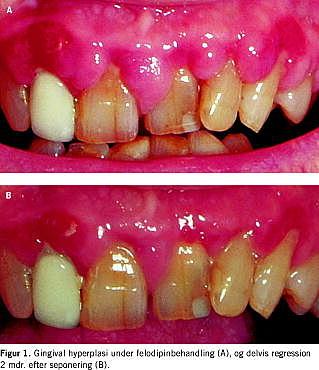

En 69-årig mand, der havde haft hypertension i tyve år og type 2-diabetes i syv år, klagede over hævet og irriteret tandkød 7 mdr. efter påbegyndt felodipinbehandling. Objektivt sås dårlig mundhygiejne, parodontitis marginalis profunda samt erytematøs og fibrotisk gingivalhyperplasi (Figur 1A ). Patienten havde nefropati med creatinin på 140 μmol/l og U-albumin/creatinin-ratio på 40 mg/mmol. Der var ingen diabetiske øjenbaggrundsforandringer. Diabetesreguleringen var god med HbA1c på 6,7%. Patienten var i antihypertensivbehandling med felodipin 10 mg, candesartan 16 mg, metoprolol 200 mg og furosemid 80 mg. Desuden blev der givet simvastatin, allopurinol, kaliumklorid, magnyl, calciumkarbonat, D-vitamin og insulin. Felodipin blev erstattet med prazocin, hvorefter den gingivale hyperplasi delvist regredierede over de følgende 2 mdr. (Figur 1B ). Patienten blev tilbudt parodontosebehandling og fjernelse af den persisterende hyperplasi i regio 7,6+.

Summary Gingival hyperplasia and calcium antagonists Ugeskr L&aelig;ger 2004;166:3828-3829 A photo-documented case of gingival hyperplasia induced by felodipine and its partial regression after two months of withdrawal is presented.